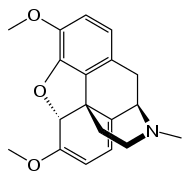

| Morphines[99] | Morphine, codeine, thebaine, sinomenine[100] | ||

Most alkaloids contain oxygen in their molecular structure; those compounds are usually colorless crystals at ambient conditions. Oxygen-free alkaloids, such as nicotine[160] or coniine,[36] are typically volatile, colorless, oily liquids.[161] Some alkaloids are colored, like berberine (yellow) and sanguinarine (orange).[161]

Most alkaloids are weak bases, but some, such as theobromine and theophylline, are amphoteric.[162] Many alkaloids dissolve poorly in water but readily dissolve in organic solvents, such as diethyl ether, chloroform or 1,2-dichloroethane. Caffeine,[163] cocaine,[164] codeine[165] and nicotine[166] are slightly soluble in water (with a solubility of ≥1g/L), whereas others, including morphine[167] and yohimbine[168] are very slightly water-soluble (0.1–1 g/L). Alkaloids and acids form salts of various strengths. These salts are usually freely soluble in water and ethanol and poorly soluble in most organic solvents. Exceptions include scopolamine hydrobromide, which is soluble in organic solvents, and the water-soluble quinine sulfate.[161]

Preparations of plants containing alkaloids and their extracts, and later pure alkaloids, have long been used as psychoactive substances. Cocaine, caffeine, and cathinone are stimulants of the central nervous system.[211][212] Mescaline and many indole alkaloids (such as psilocybin, dimethyltryptamine and ibogaine) have hallucinogenic effect.[213][214] Morphine and codeine are strong narcotic pain killers.[215]